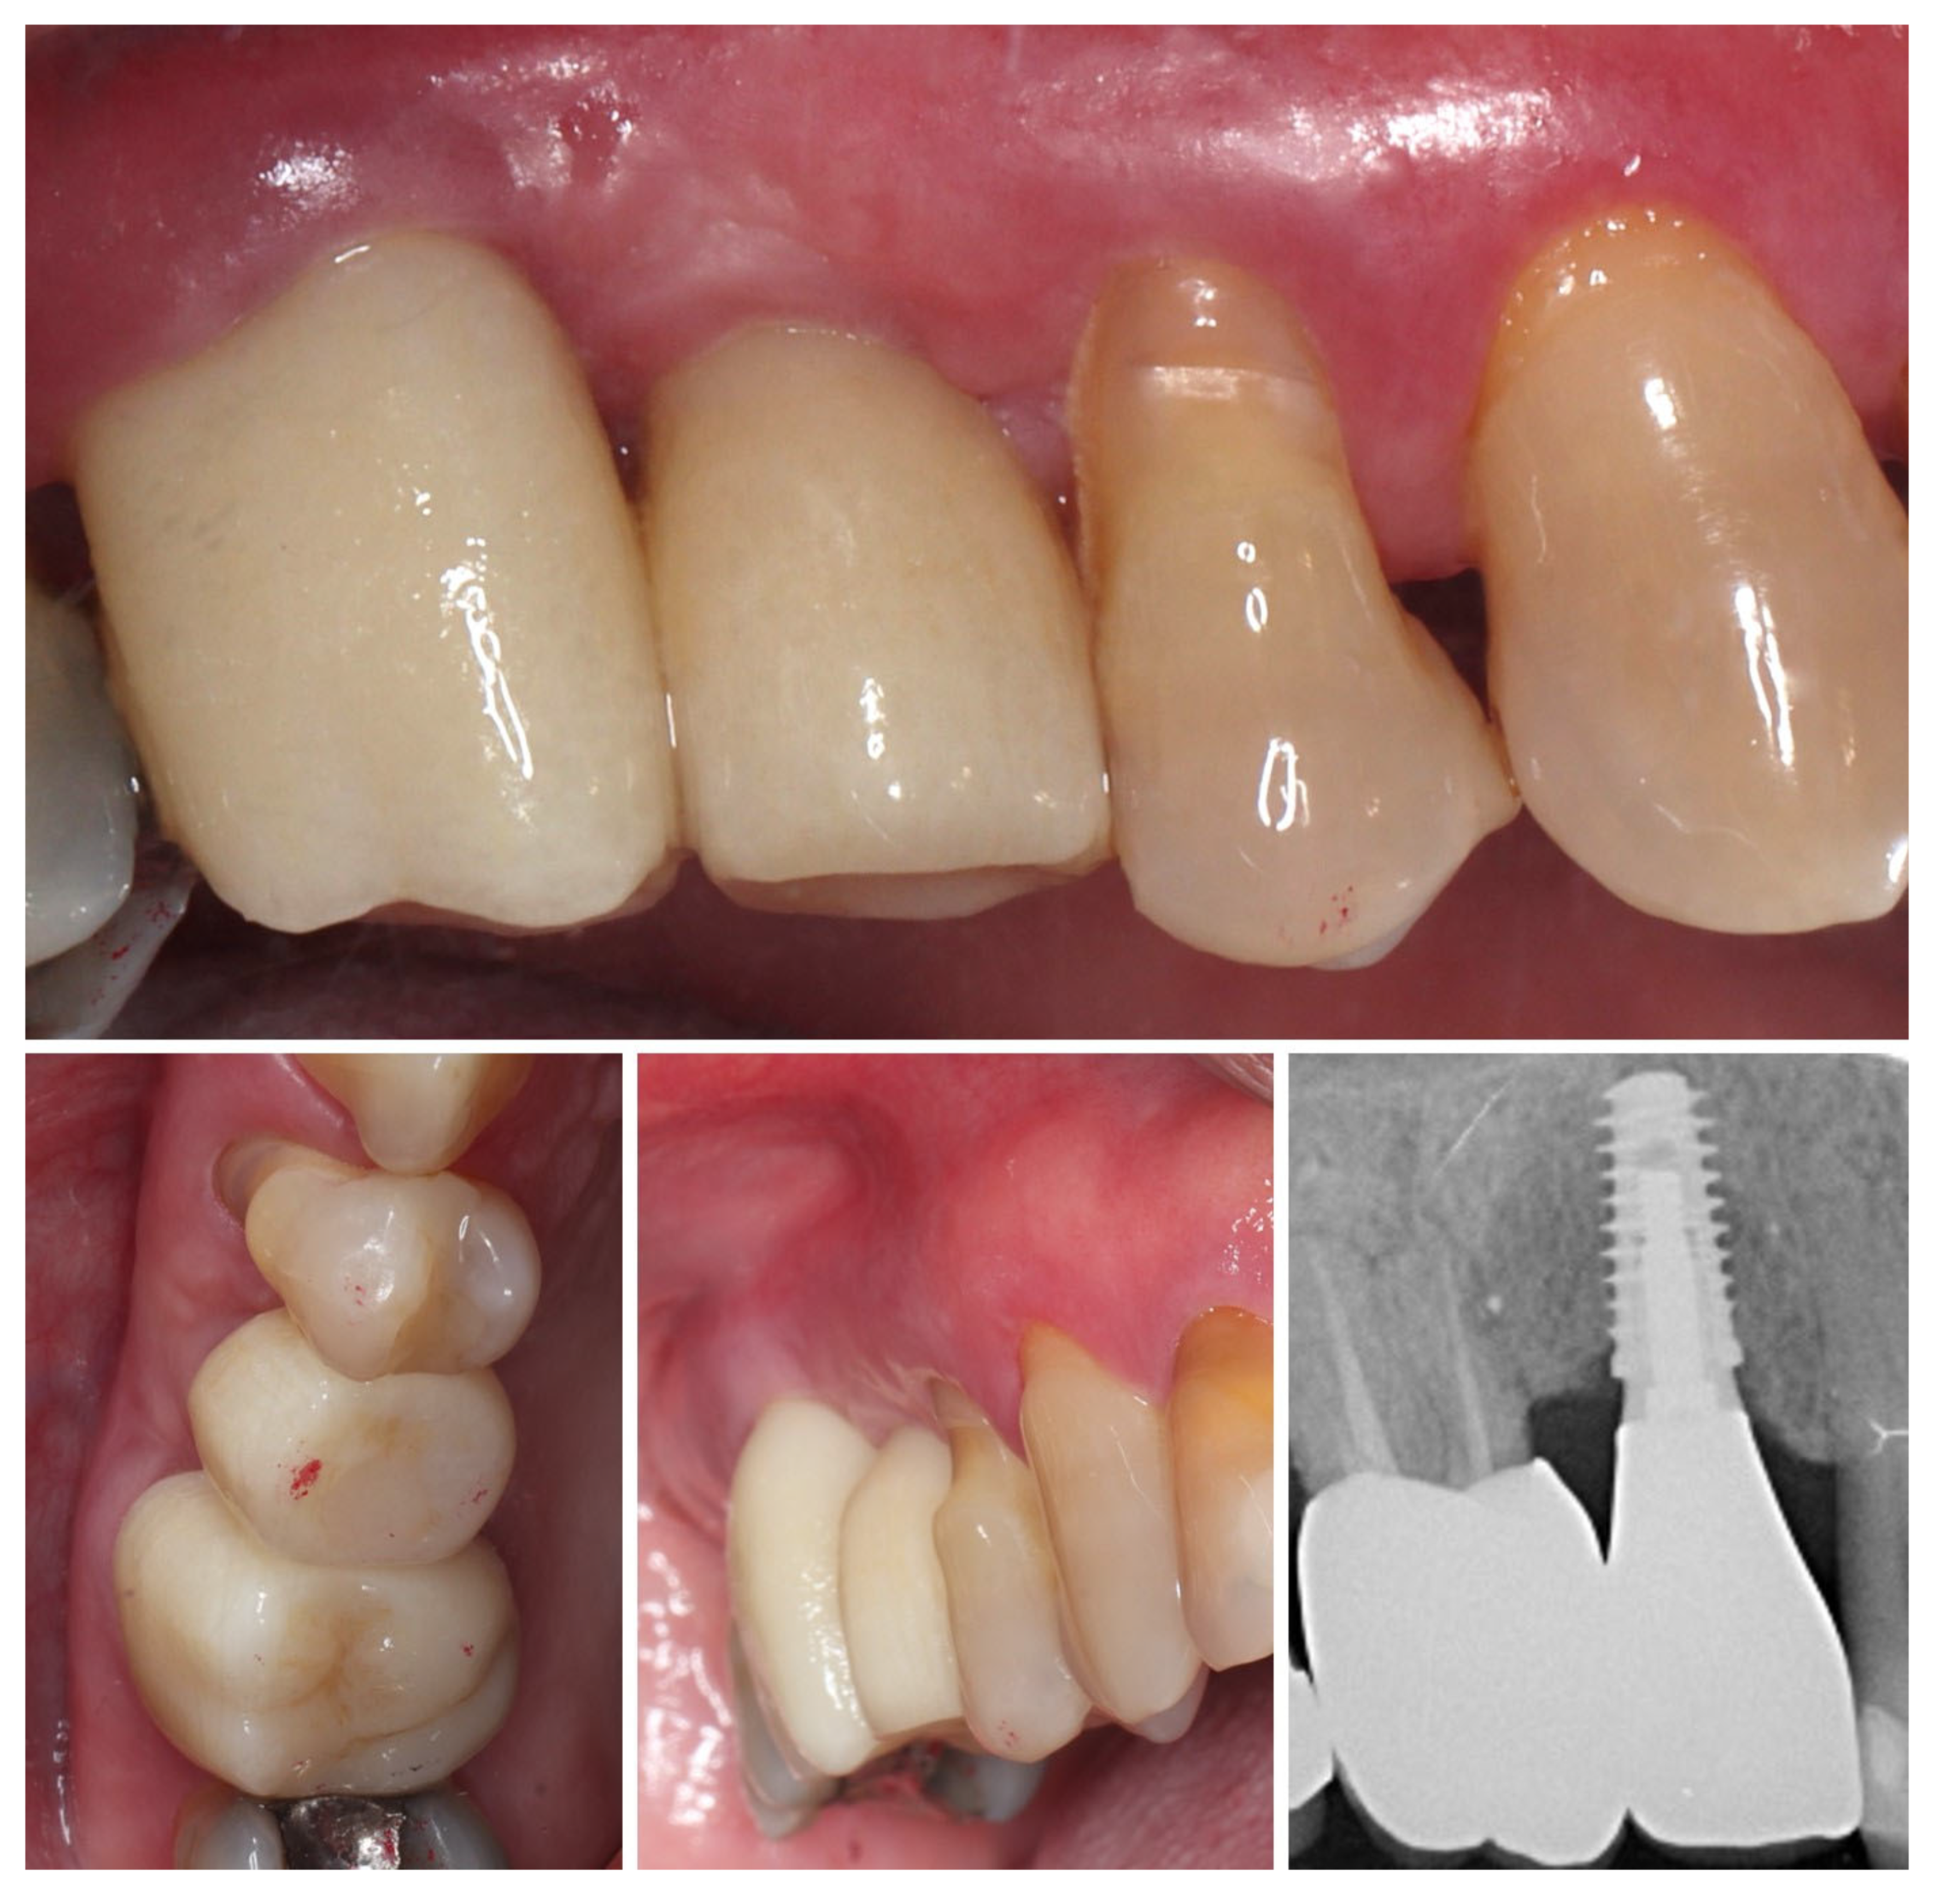

| Timepoint | Horizontal Thickness (mm) | Vertical Thickness (mm) | Clinical/Radiographic Findings | |

|---|---|---|---|---|

| 1 | Baseline (Day 0) | 2.3 | 2.4 | Initial thin buccal tissue |

| 2 | 2 weeks post-op | Uneventful healing, stable mucosal margin | ||

| 3 | 3 months post-op (with provisional) | 3.4 | 3.4 | Increased thickness, stable bone and mucosa |

| 4 | 4 months post-provisional | 3.5 | 3.6 | Stable peri-implant mucosa around provisional crown |

| 5 | 8 months post-op (final crown) | 3.5 | 4.1 | Final crown placed, harmonious soft tissue contours, and stable crestal bone |

| 6 | 14 months post-definitive | Long-term stability of soft tissue and crestal bone confirmed |